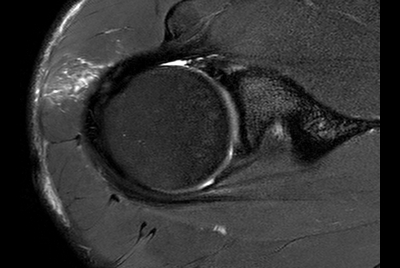

Shoulder with oncologic mass